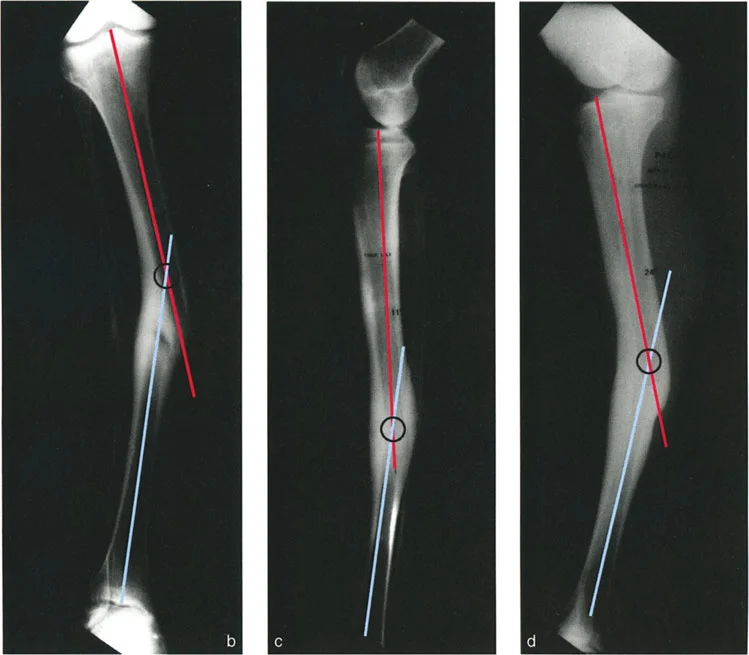

تشوهات المستوى المائل بزاوية 90 درجة

هنا، تحدث التشوهات في مستويين مائلين غير تشريحيين، لكنهما متعامدان (بزاوية 90 درجة) على بعضهما البعض. تظهر الأشعة السينية الأمامية والخلفية (AP) والجانبية (LAT) انحرافًا وانزياحًا. العلامة المميزة هي أن مركز دوران الانحراف (CORA) يقع في مستويات مختلفة على الأشعة السينية الأمامية والخلفية (AP) والجانبية (LAT)؛ أحدهما قريب من الكسر والآخر بعيد عنه.

يمكن أن تظهر الأشعة السينية المائلة، التي تُؤخذ عموديًا على مستوى أقصى انحراف، انحرافًا بدون انزياح. وبالمثل، تظهر الأشعة السينية المائلة الأخرى، العمودية على مستوى أقصى انزياح، انزياحًا بدون انحراف. في هذه الحالة، يكون مركز دوران الانحراف (CORA) على الأشعة المائلة التي تظهر أقصى انحراف عند مستوى الكسر.

مثال: التئام خاطئ لعظم الساق الأيسر يظهر انحرافًا وانزياحًا في مستويين مائلين مختلفين ومتعامدين.

تظهر الأشعة السينية المائلة في هذه الحالات أن في مستوى أقصى انحراف لا يوجد انزياح، وأن في مستوى أقصى انزياح لا يوجد انحراف. وهذا يؤكد تعامد المستويين.

التصوير الشعاعي بالأشعة السينية

تُعد الأشعة السينية (X-rays) الأداة الأساسية لتشخيص تشوهات العظام. يتم أخذ صور متعددة للطرف المصاب من زوايا مختلفة (الأمامية الخلفية، الجانبية، والمائلة) لتقييم التشوه في جميع المستويات. الأستاذ الدكتور محمد هطيف يولي اهتمامًا خاصًا لجودة هذه الصور ودقتها، حيث إنها الأساس الذي يُبنى عليه التحليل البيوميكانيكي.

تحليل CORA لتحديد مركز الدوران الفعلي

يُعد تحليل مركز دوران الانحراف (CORA - Center of Rotation of Angulation) حجر الزاوية في التخطيط الجراحي لتصحيح تشوهات العظام. يتطلب هذا التحليل فهمًا عميقًا للبيوميكانيكا العظمية وخبرة كبيرة، وهو ما يتميز به الأستاذ الدكتور محمد هطيف.

- ما هو CORA؟ هو النقطة الافتراضية التي يدور حولها الجزء البعيد من العظم بالنسبة للجزء القريب لتصحيح الانحراف.

- كيف يتم تحديده؟ يتم تحديد CORA برسم خطوط محورية على الأشعة السينية (AP و LAT) لكل جزء من العظم المشوه (القريب والبعيد). نقطة تقاطع هذه الخطوط هي CORA.

- أهميته: تحديد CORA بدقة يُمكّن الجراح من تخطيط قطع العظم (Osteotomy) في الموقع الأمثل. إذا تم إجراء قطع العظم عند مستوى CORA، يمكن تصحيح الانحراف بحركة زاويّة واحدة دون إحداث انزياح جديد أو زيادة الانزياح الموجود. هذا يقلل من تعقيد الجراحة ويحسن النتائج الوظيفية.